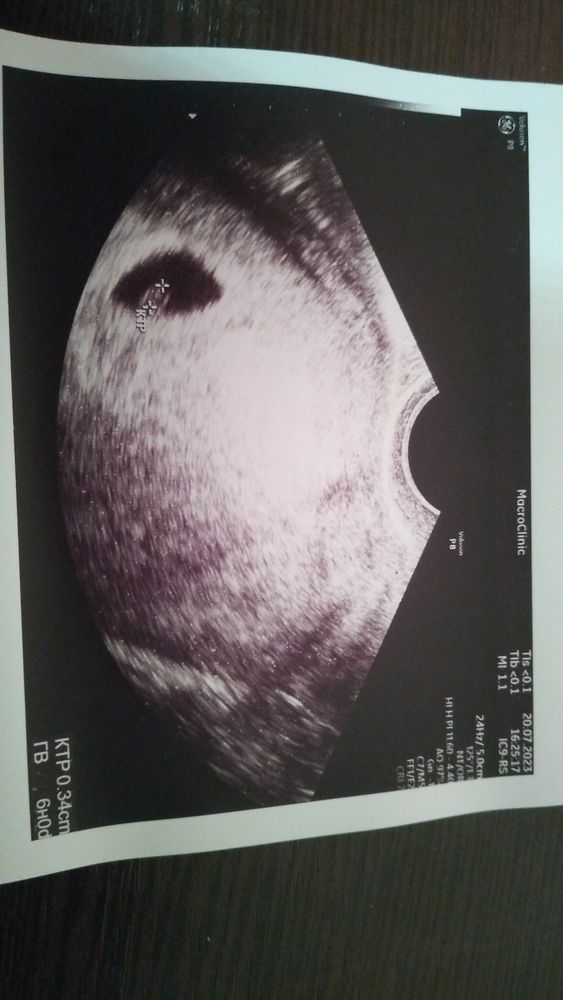

Мама мальчика (1 год), жду мальчика, 8 неделя

Узи 5н6д..

Мой маленький малыш🤍